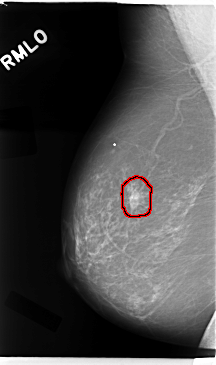

C_0016_1.RIGHT_MLO

RIGHT_MLO LINES 4736 PIXELS_PER_LINE 2800 BITS_PER_PIXEL 12 RESOLUTION 50 OVERLAY

FILE: C_0016_1.RIGHT_MLO.OVERLAY

TOTAL_ABNORMALITIES 1

ABNORMALITY 1

LESION_TYPE MASS SHAPE IRREGULAR MARGINS SPICULATED

ASSESSMENT 5

SUBTLETY 5

PATHOLOGY MALIGNANT

TOTAL_OUTLINES 1

BOUNDARY